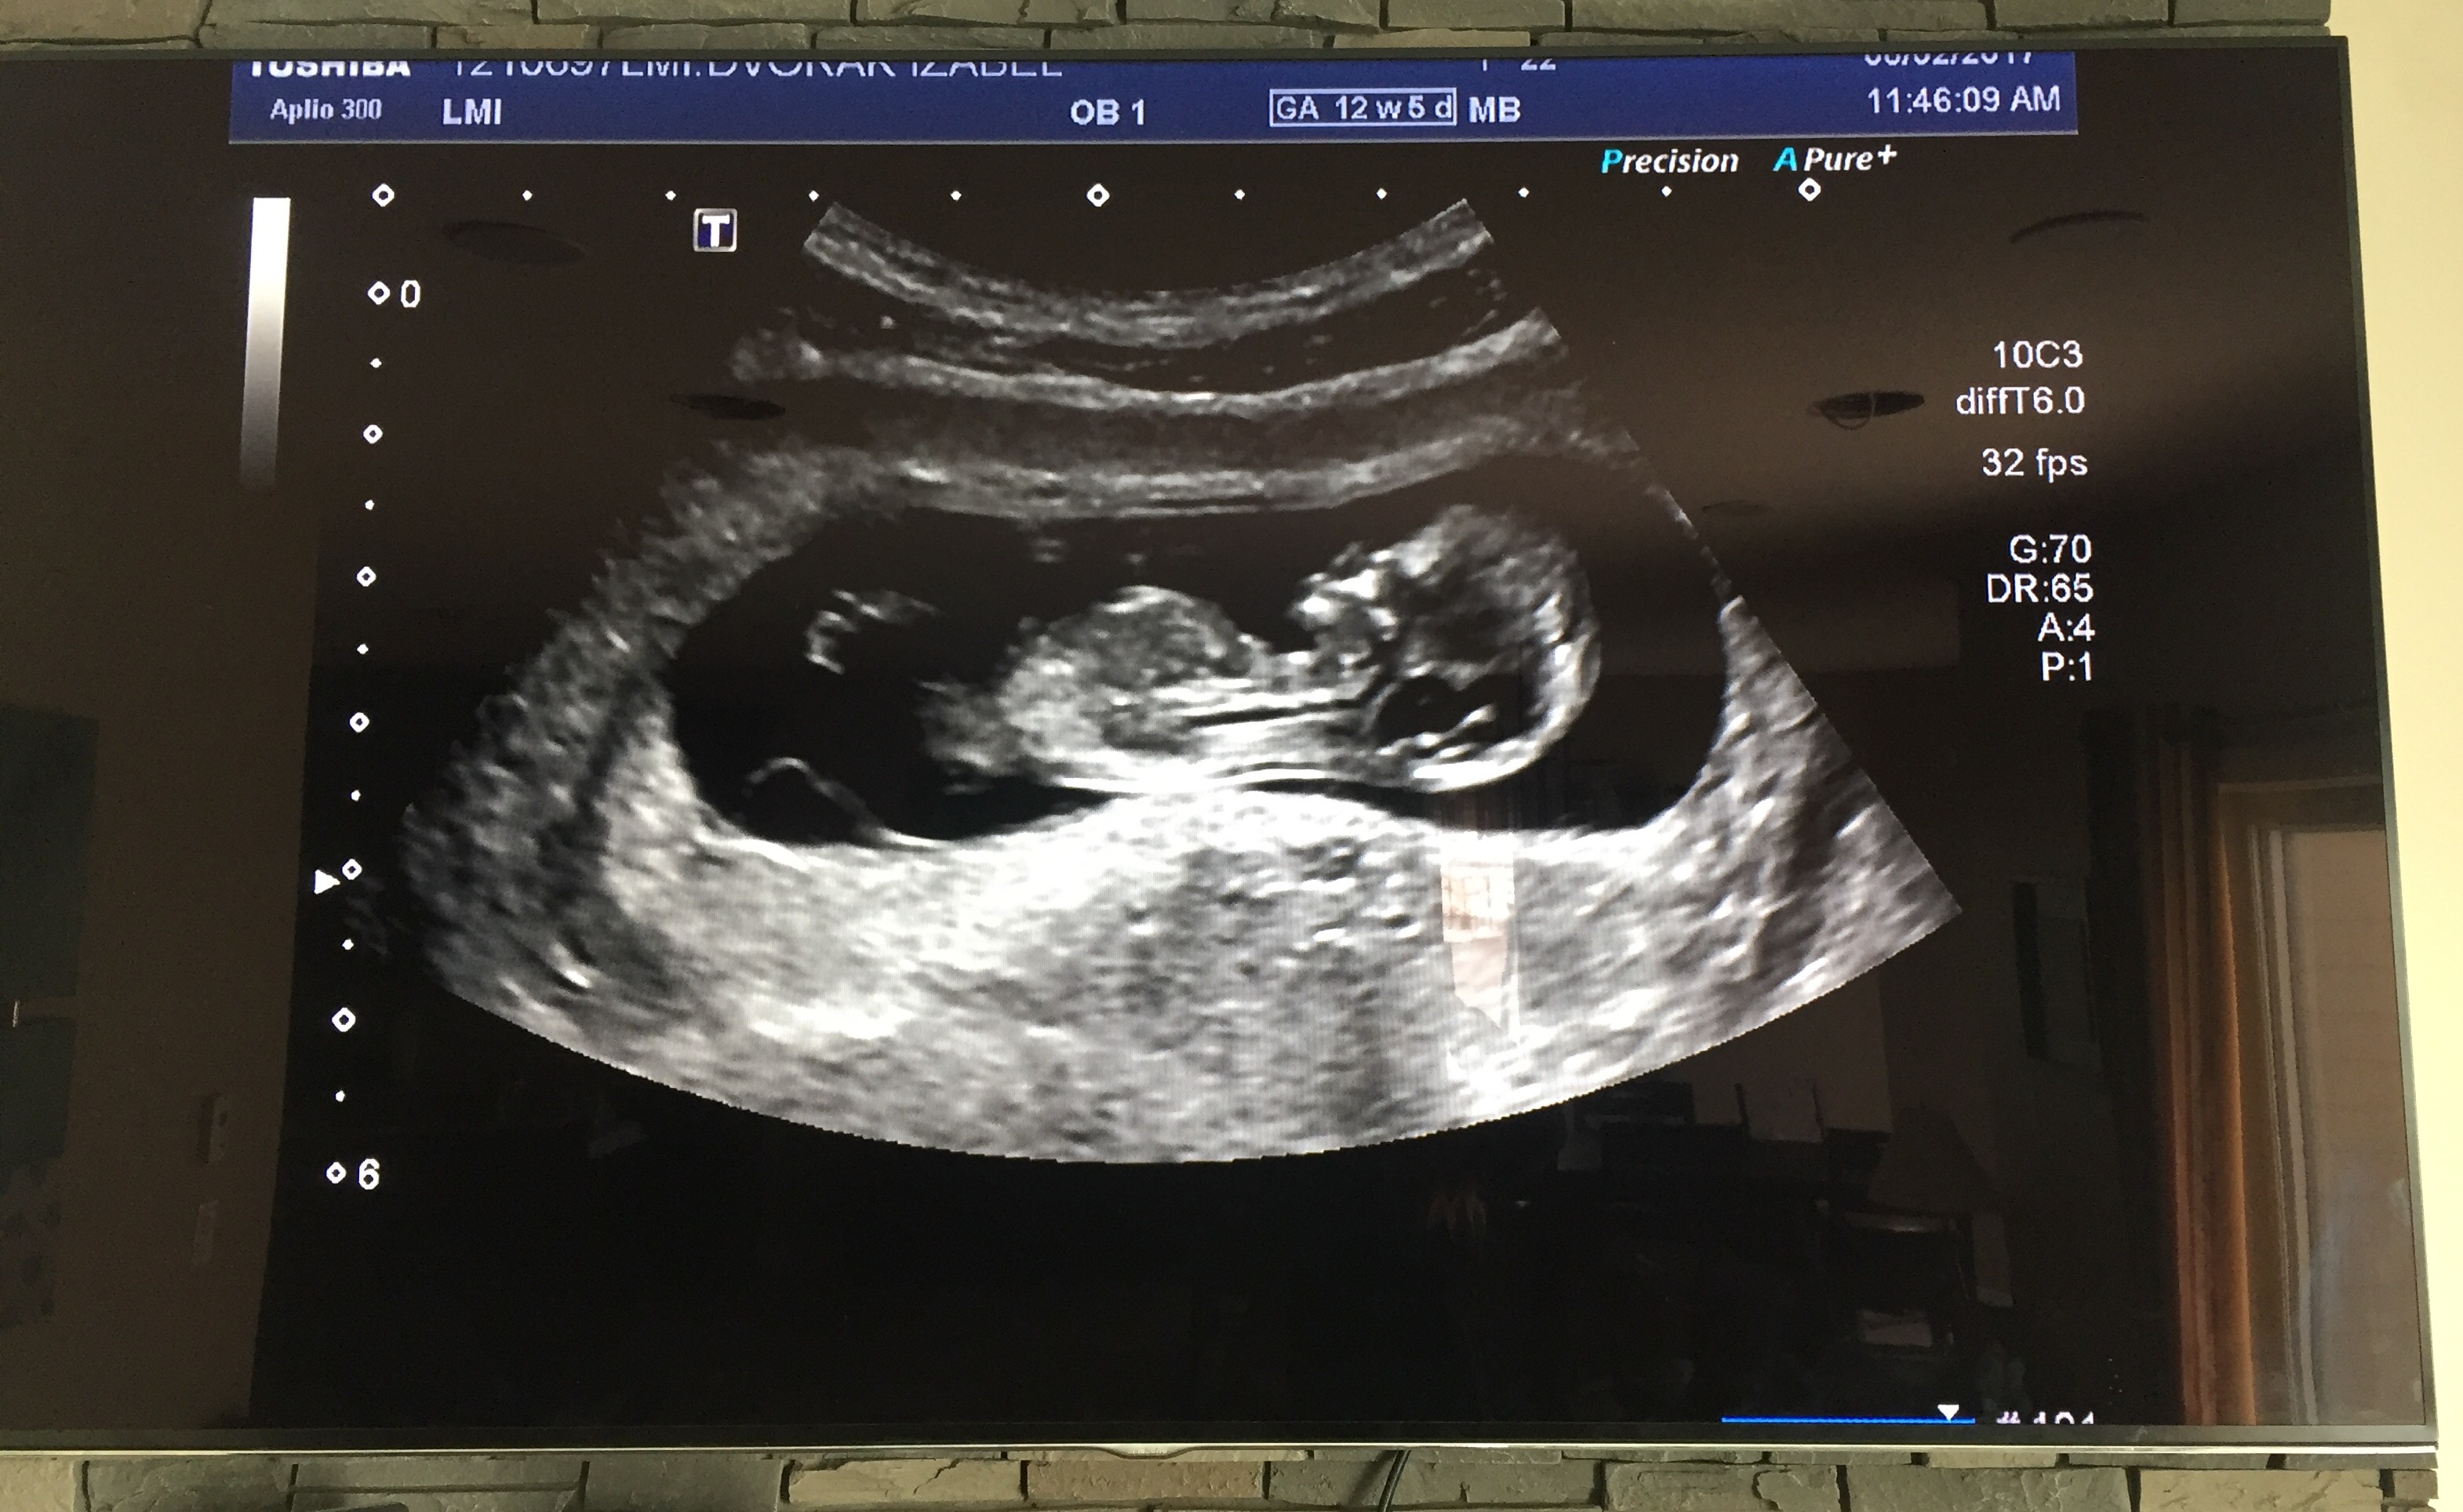

We thought I was 12w5d but I am measuring at 11w1d! does that look like the nub? If so any guesses? Also open to skull theory guesses too! :)Attachment 34883

I'm not sure there is a visible nub there, and 11+1 is too early, even though the baby looks more like a 12 weeker.